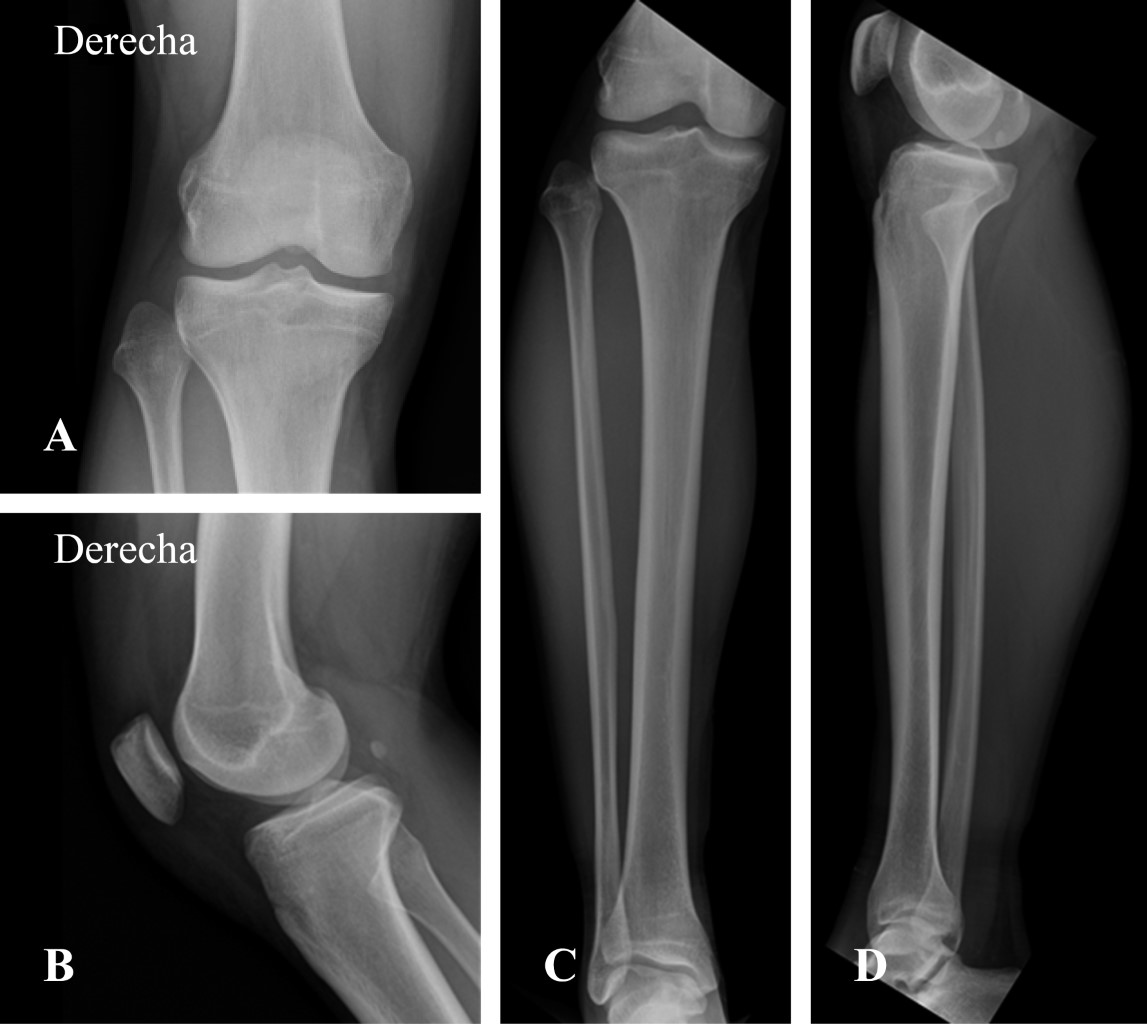

Webthe tibiofibular joints are a set of articulations that unite the tibia and fibula. These two bones of the leg are connected via three junctions; Como eu mencionei anteriormente, ela também se. Web3. 2 preoperative detumescence time and daily swelling value. The preoperative detumescence time of the calcaneal distraction group was significantly. Weba luxação da articulação tibiofibular proximal ocorre mais comumente quando o atleta sofre um impacto ou cai com o joelho em uma posição. Weba articulação tibiofibular proximal é articulação sinovial entre côndilo tibial lateral e cabeça da fíbula. Ao menos 10% da população possui comunicação entre esta. Webthe proximal tibiofibular joint is formed by an articulation between the head of the fibula and the lateral condyle of the tibia. It is a plane type synovial joint;.

Uma forte estrutura fibrosa, a membrana interóssea, conecta a tíbia e a fíbula ao longo do comprimento dos dois ossos. Proximalmente, essa estrutura é reforçada por fortes ligamentos anterior e posterior e forma uma articulação. Webluxação da articulação tibiofibular proximal. A tibiofibular é articulação naturalmente estável devido à congruência óssea articular, ao envelope musculoligamentar e sua.